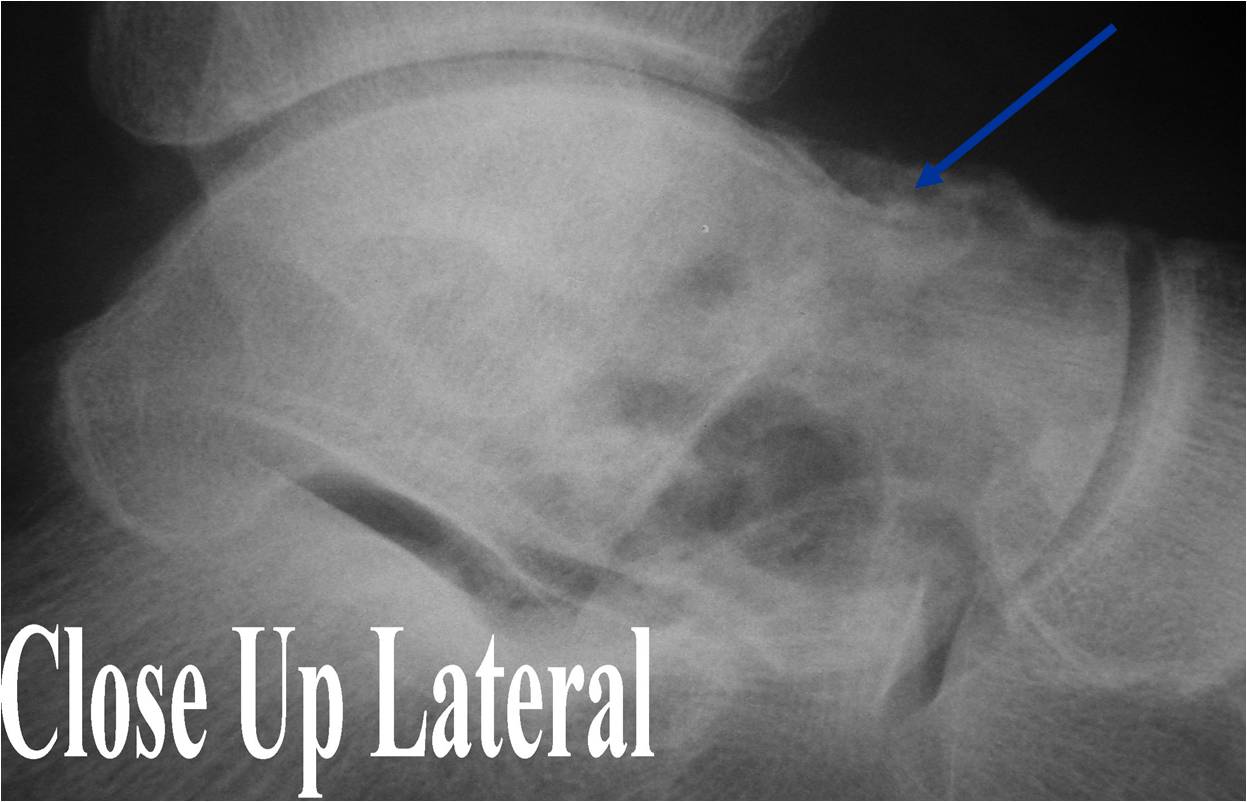

Bone Tumors Clues And Cues - LearningRadiology

Bone Tumors Clues and Cues William Herring, M.D. © 2002 In Slide Show mode, advance the slides by pressing the spacebar All Photos Retain the Copyright of their Authors. Clues by Appearance of Lesion. Patterns of Bone Destruction OGeographic OMoth-eaten ... Access Full Source